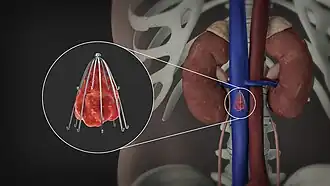

An inferior vena cava filter is a medical device made of metal that is implanted by vascular surgeons or interventional radiologists into the inferior vena cava to prevent a life-threatening pulmonary embolism (PE) or venous thromboembolism (VTE).[2][3]

The filter is designed to trap a blood clot and prevent its travel to the lung where it would form a pulmonary embolism.[4][3] Their effectiveness and safety profile is well established, and they may be used when anticoagulant treatment is not sufficient.[5]

Placement

IVC filters are placed endovascularly, meaning that they are inserted via the blood vessels. Historically, IVC filters were placed surgically, but with modern filters that can be compressed into much thinner catheters, access to the venous system can be obtained via the femoral vein (the large vein in the groin), the internal jugular vein (the large vein in the neck) or the arm veins with one design. Choice of route depends mainly on the number and location of any blood clot within the venous system. To place the filter, a catheter is guided into the IVC using fluoroscopic guidance, then the filter is pushed through the catheter and deployed into the desired location, usually just below the junction of the IVC and the lowest renal vein.[44]

Review of prior cross-sectional imaging or a venogram of the IVC is performed before deploying the filter to assess for potential anatomic variations, thrombi within the IVC, or areas of stenoses, as well as to estimate the diameter of the IVC. Rarely, ultrasound-guided placement is preferred in the setting of contrast allergy, chronic kidney disease, and when patient immobility is desired. The size of the IVC may affect which filter is deployed, as some (such as the Birds Nest) are approved to accommodate larger cavae. There are situations where the filter is placed above the renal veins (e.g. pregnant patients or women of childbearing age, renal or gonadal vein thromboses, etc.). Also, if there is duplication of the IVC, the filter is placed above the confluence of the two IVCs [45] or a filter can be placed within each IVC.[46]